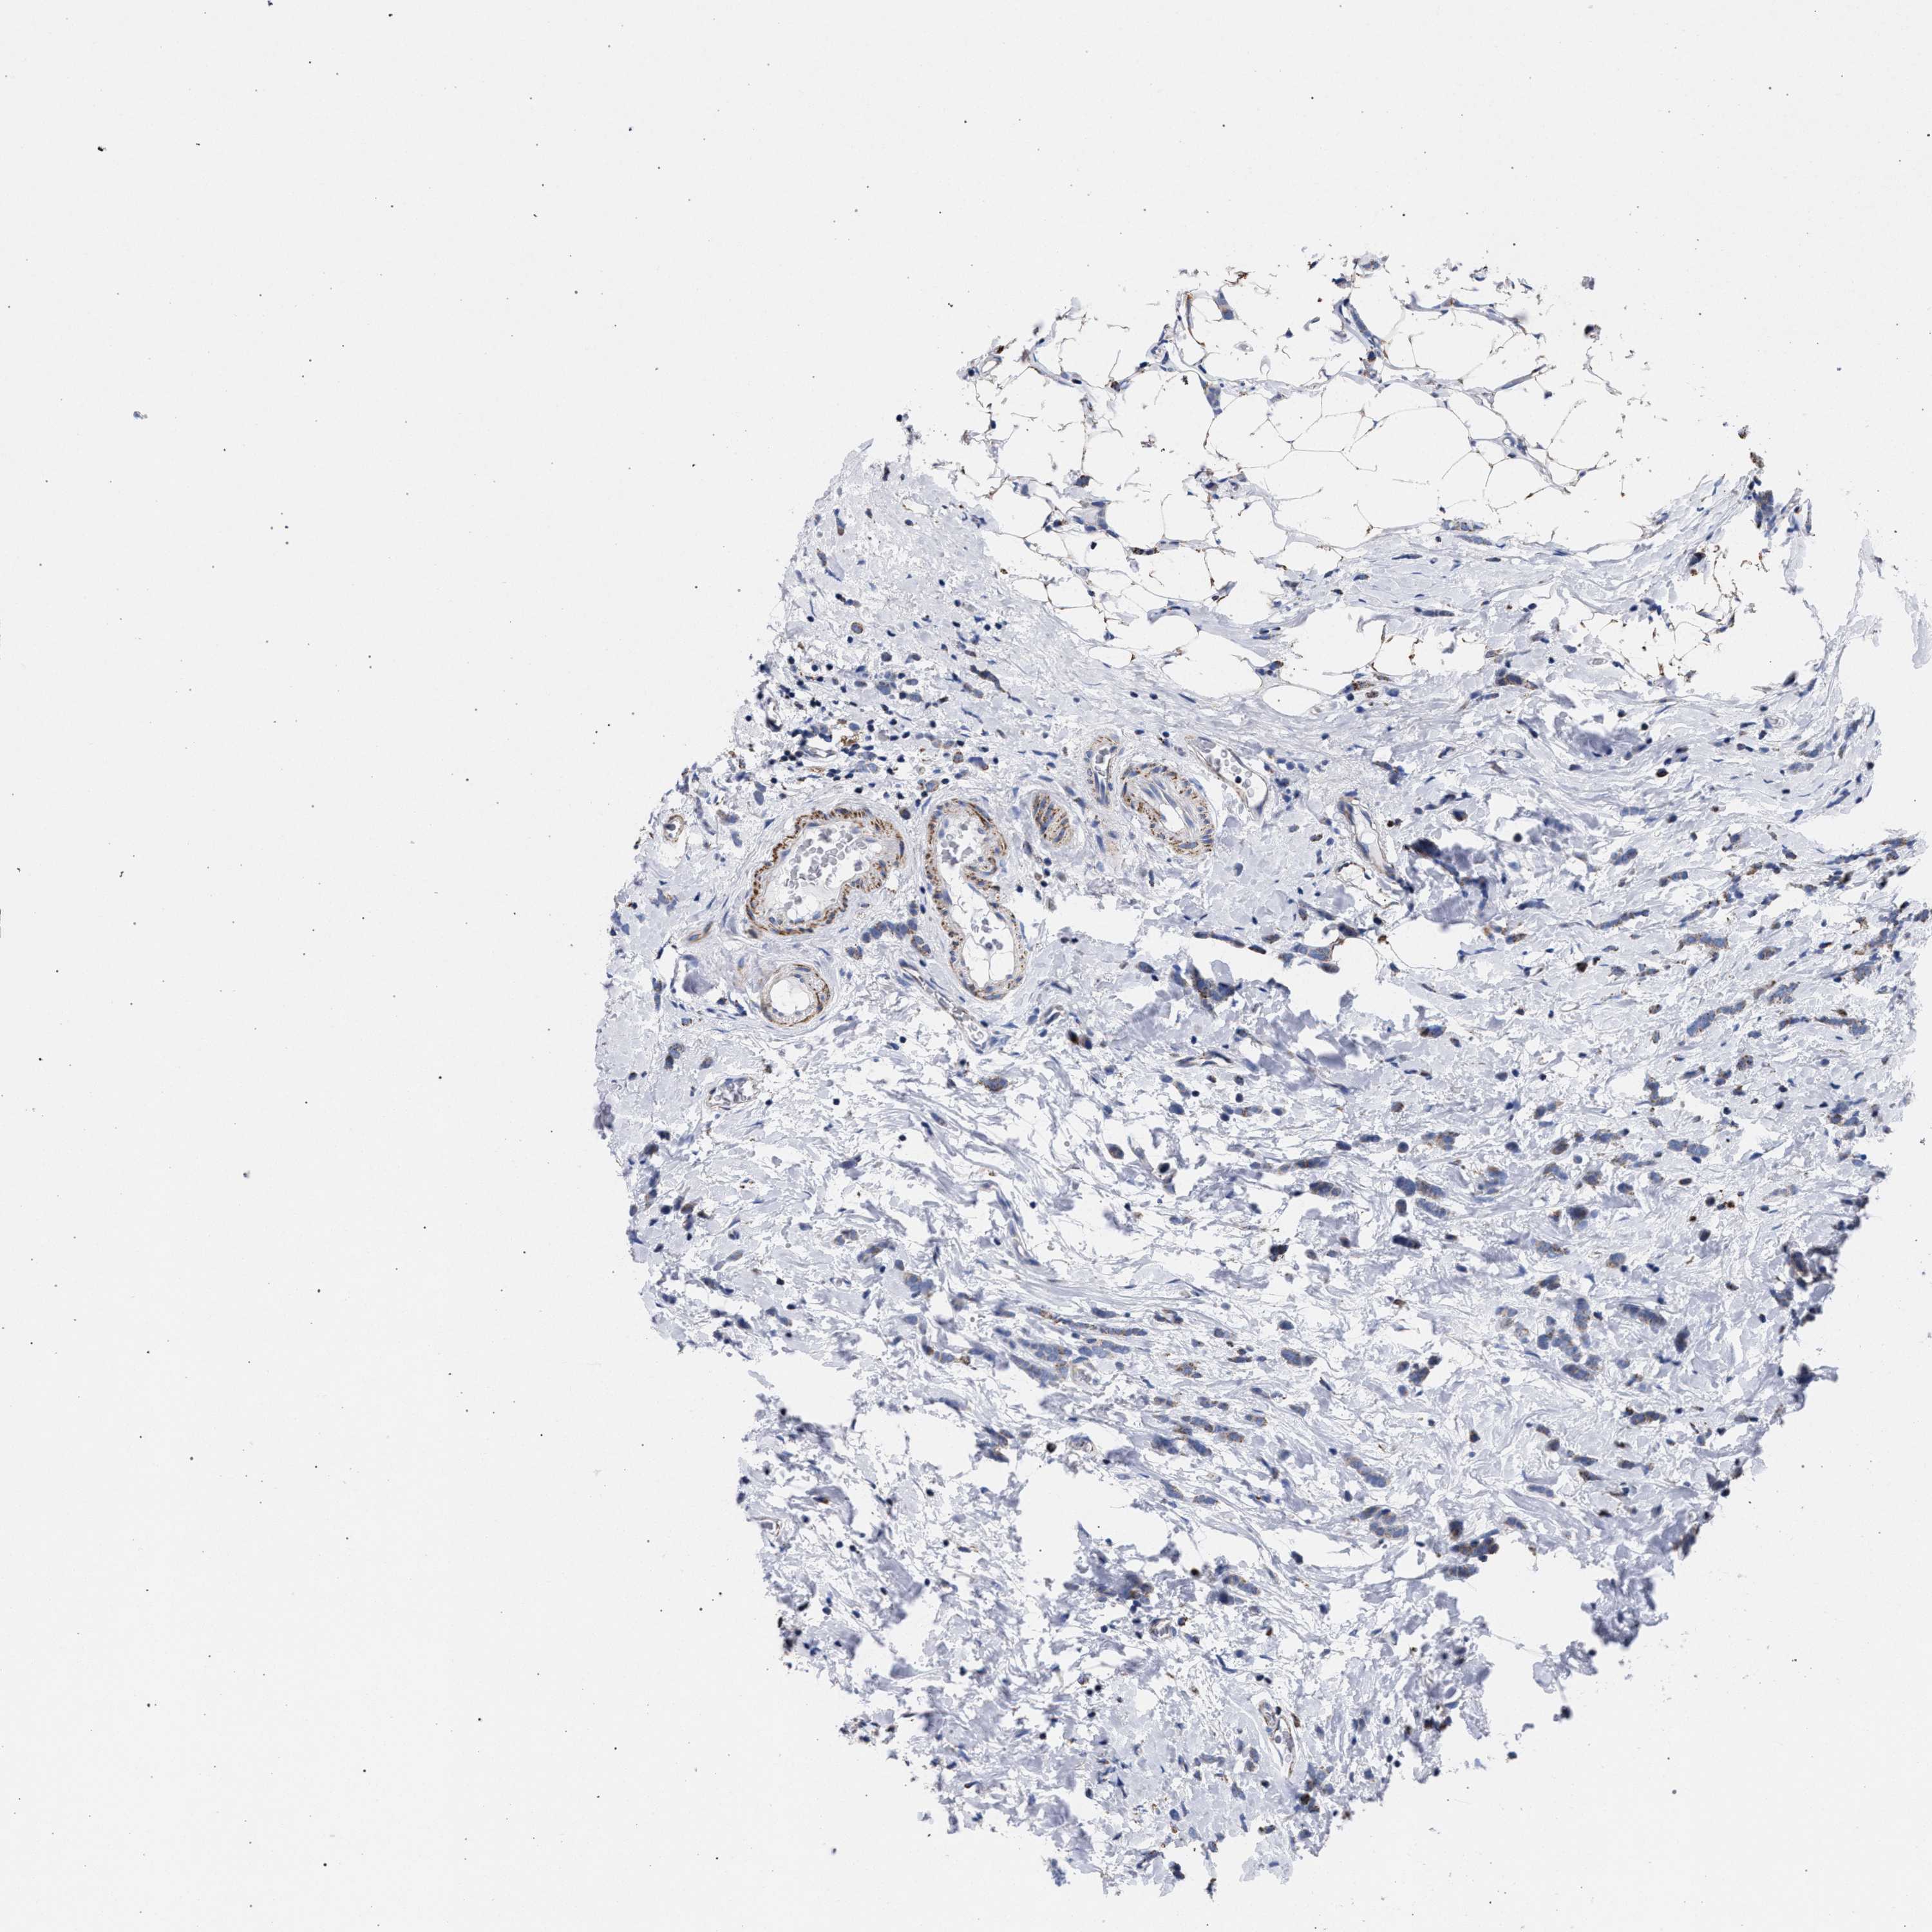

BRCA TCGA BRCA VALIDATION PROTEIN EXPRESSION

ANTIBODIES

AND

VALIDATION